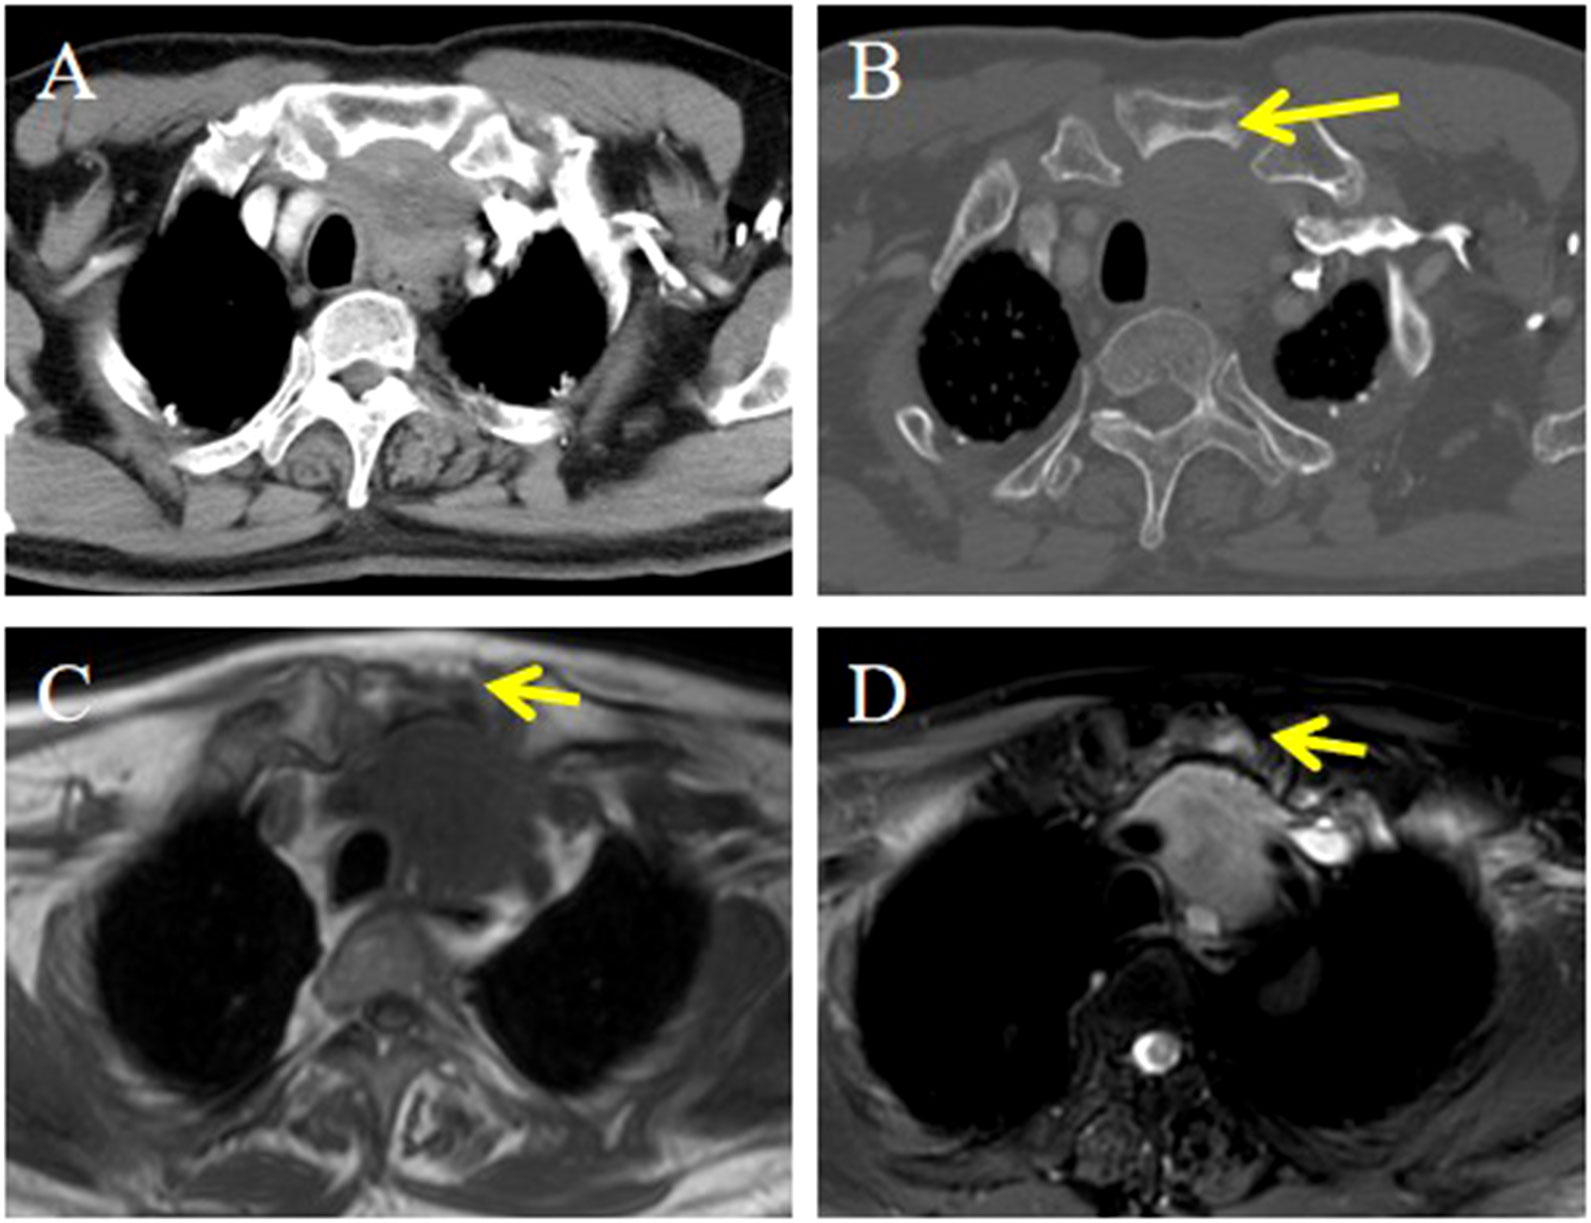

Objective: To summarize the clinical characteristics and imaging features of intrathyroid thymic carcinoma (ITTC), along with diagnostic and therapeutic approaches, to increase awareness of this rare disease. Methods: We retrospectively analyzed 14 patients with ITTC confirmed by core needle biopsy (CNB) and surgery combined with immunohistochemistry. The clinical and imaging findings, treatment, pathological findings and follow-up data of these patients were reviewed. Results: Thirteen patients were newly diagnosed and one relapsed at the original surgical site. All tumors were solitary, mostly located in the lower neck or upper chest, often in the tracheoesophageal groove with or without extension to the thyroid’s lower pole, and approximately two-thirds of patients presented with hoarseness. On CT, most lesions appeared as irregular, low-density soft-tissue masses, with calcification in two cases; contrast-enhanced CT revealed mild heterogeneous or homogeneous enhancement, and over half exhibited an arc-shaped interface with adjacent thyroid tissue. Most tumors were locally advanced, invading muscles, the supraclavicular fossa, tracheoesophageal groove, esophagus, tracheal wall, or mediastinal vessels. The diagnostic accuracy of fine-needle aspiration biopsy (FNAB) was low, whereas core needle biopsy (CNB) combined with immunohistochemistry was reliable. Ten patients underwent radical surgery, of whom three received adjuvant chemoradiotherapy and four adjuvant radiotherapy; four patients received radical chemoradiotherapy, and one received combined therapy including anlotinib, a novel tyrosine kinase inhibitor. The median follow-up was 86 months (range, 25–146), and three surgically treated patients developed local recurrence or pulmonary metastasis. Conclusion: CNB combined with immunohistochemistry is recommended when the characteristic and imaging manifestations suggest a diagnosis of ITTC. Especially for locally advanced cases, imaging-based diagnosis can be useful for analysis and to guide treatment.